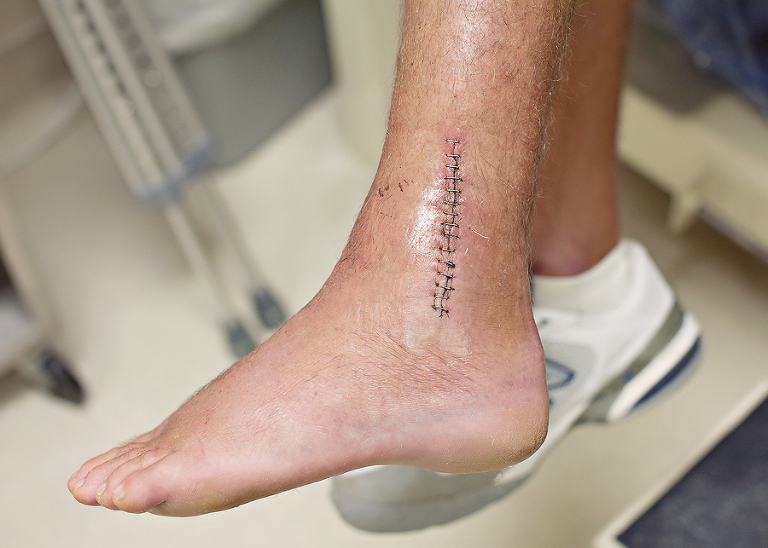

During the surgery, his doctor fixed it all up with some hardware, stapled him up, and put a cast on. I won’t bore you with the details of how awful he was to those poor nurses in recovery, or how when he found out I was only allowed 10 minutes back to see him every 4 hours he started pulling off wires and cussing. I certainly won’t explain how the nurses had to call his doctor at his request less than 2 hours after surgery and ask if he could be released to go home when he really should have stayed the night. I definitely won’t disclose that those same poor nurses couldn’t kick his ass out fast enough, and had him safely buckled in my front seat 10 minutes later heading back to Ocean Springs. Good times, good times… Scott’s cast stayed on for 10 days, then we went back to have the staples removed.

The doctor said that everything looked great, and he was right where he needed to be as far as recovery goes.